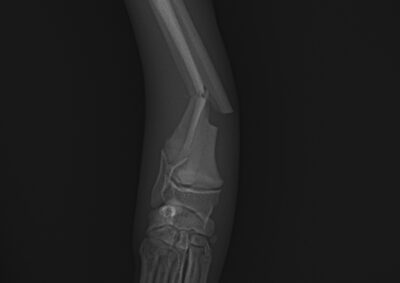

整形外科 注意 ボタンをクリックした先に、治療中および手術中の画像が説明で使用されている場合がございます。 そのような画像に弱い方は閲覧なさらないようお願いいたします。 整形外科 上腕骨外顆骨折の癒合不全 整形外科 大腿骨遠位開放および粉砕骨折 整形外科 膝蓋骨内方脱臼+前十字靭帯断裂 PGR#21+CBLO #251 整形外科 犬の前十字靭帯断裂に対するCBLO #250 整形外科 脛骨粉砕骨折 整形外科 内側鉤状突起分離症(Fragmented Medial Coronoid Process:F... 整形外科 股関節全置換術(トータル・ヒップ・リプレイスメント)#27 整形外科 橈骨固定術 #268 整形外科 橈骨固定術 #267 整形外科 橈骨固定術 #266 整形外科 股関節脱臼に対するBUSTOR #67 整形外科 脛骨粗面剥離骨折 <1234567> 症例カテゴリー 放射線治療整形外科軟部組織外科脳神経外科内科腫瘍外科救急・集中治療リハビリテーション科腫瘍内科内視鏡科脳神経科呼吸器外科中医・漢方猫の腎移植循環器科